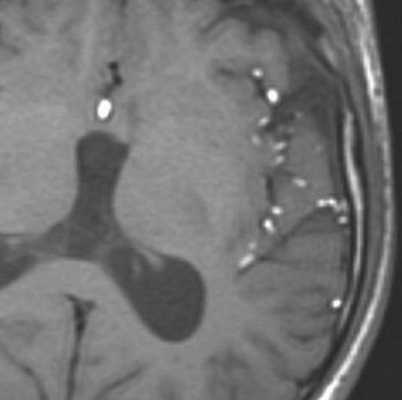

МРТ головного мозга. Т1-взвешенные корональная и сагиттальная МРТ. Эпидермоидная киста левой височной доли.